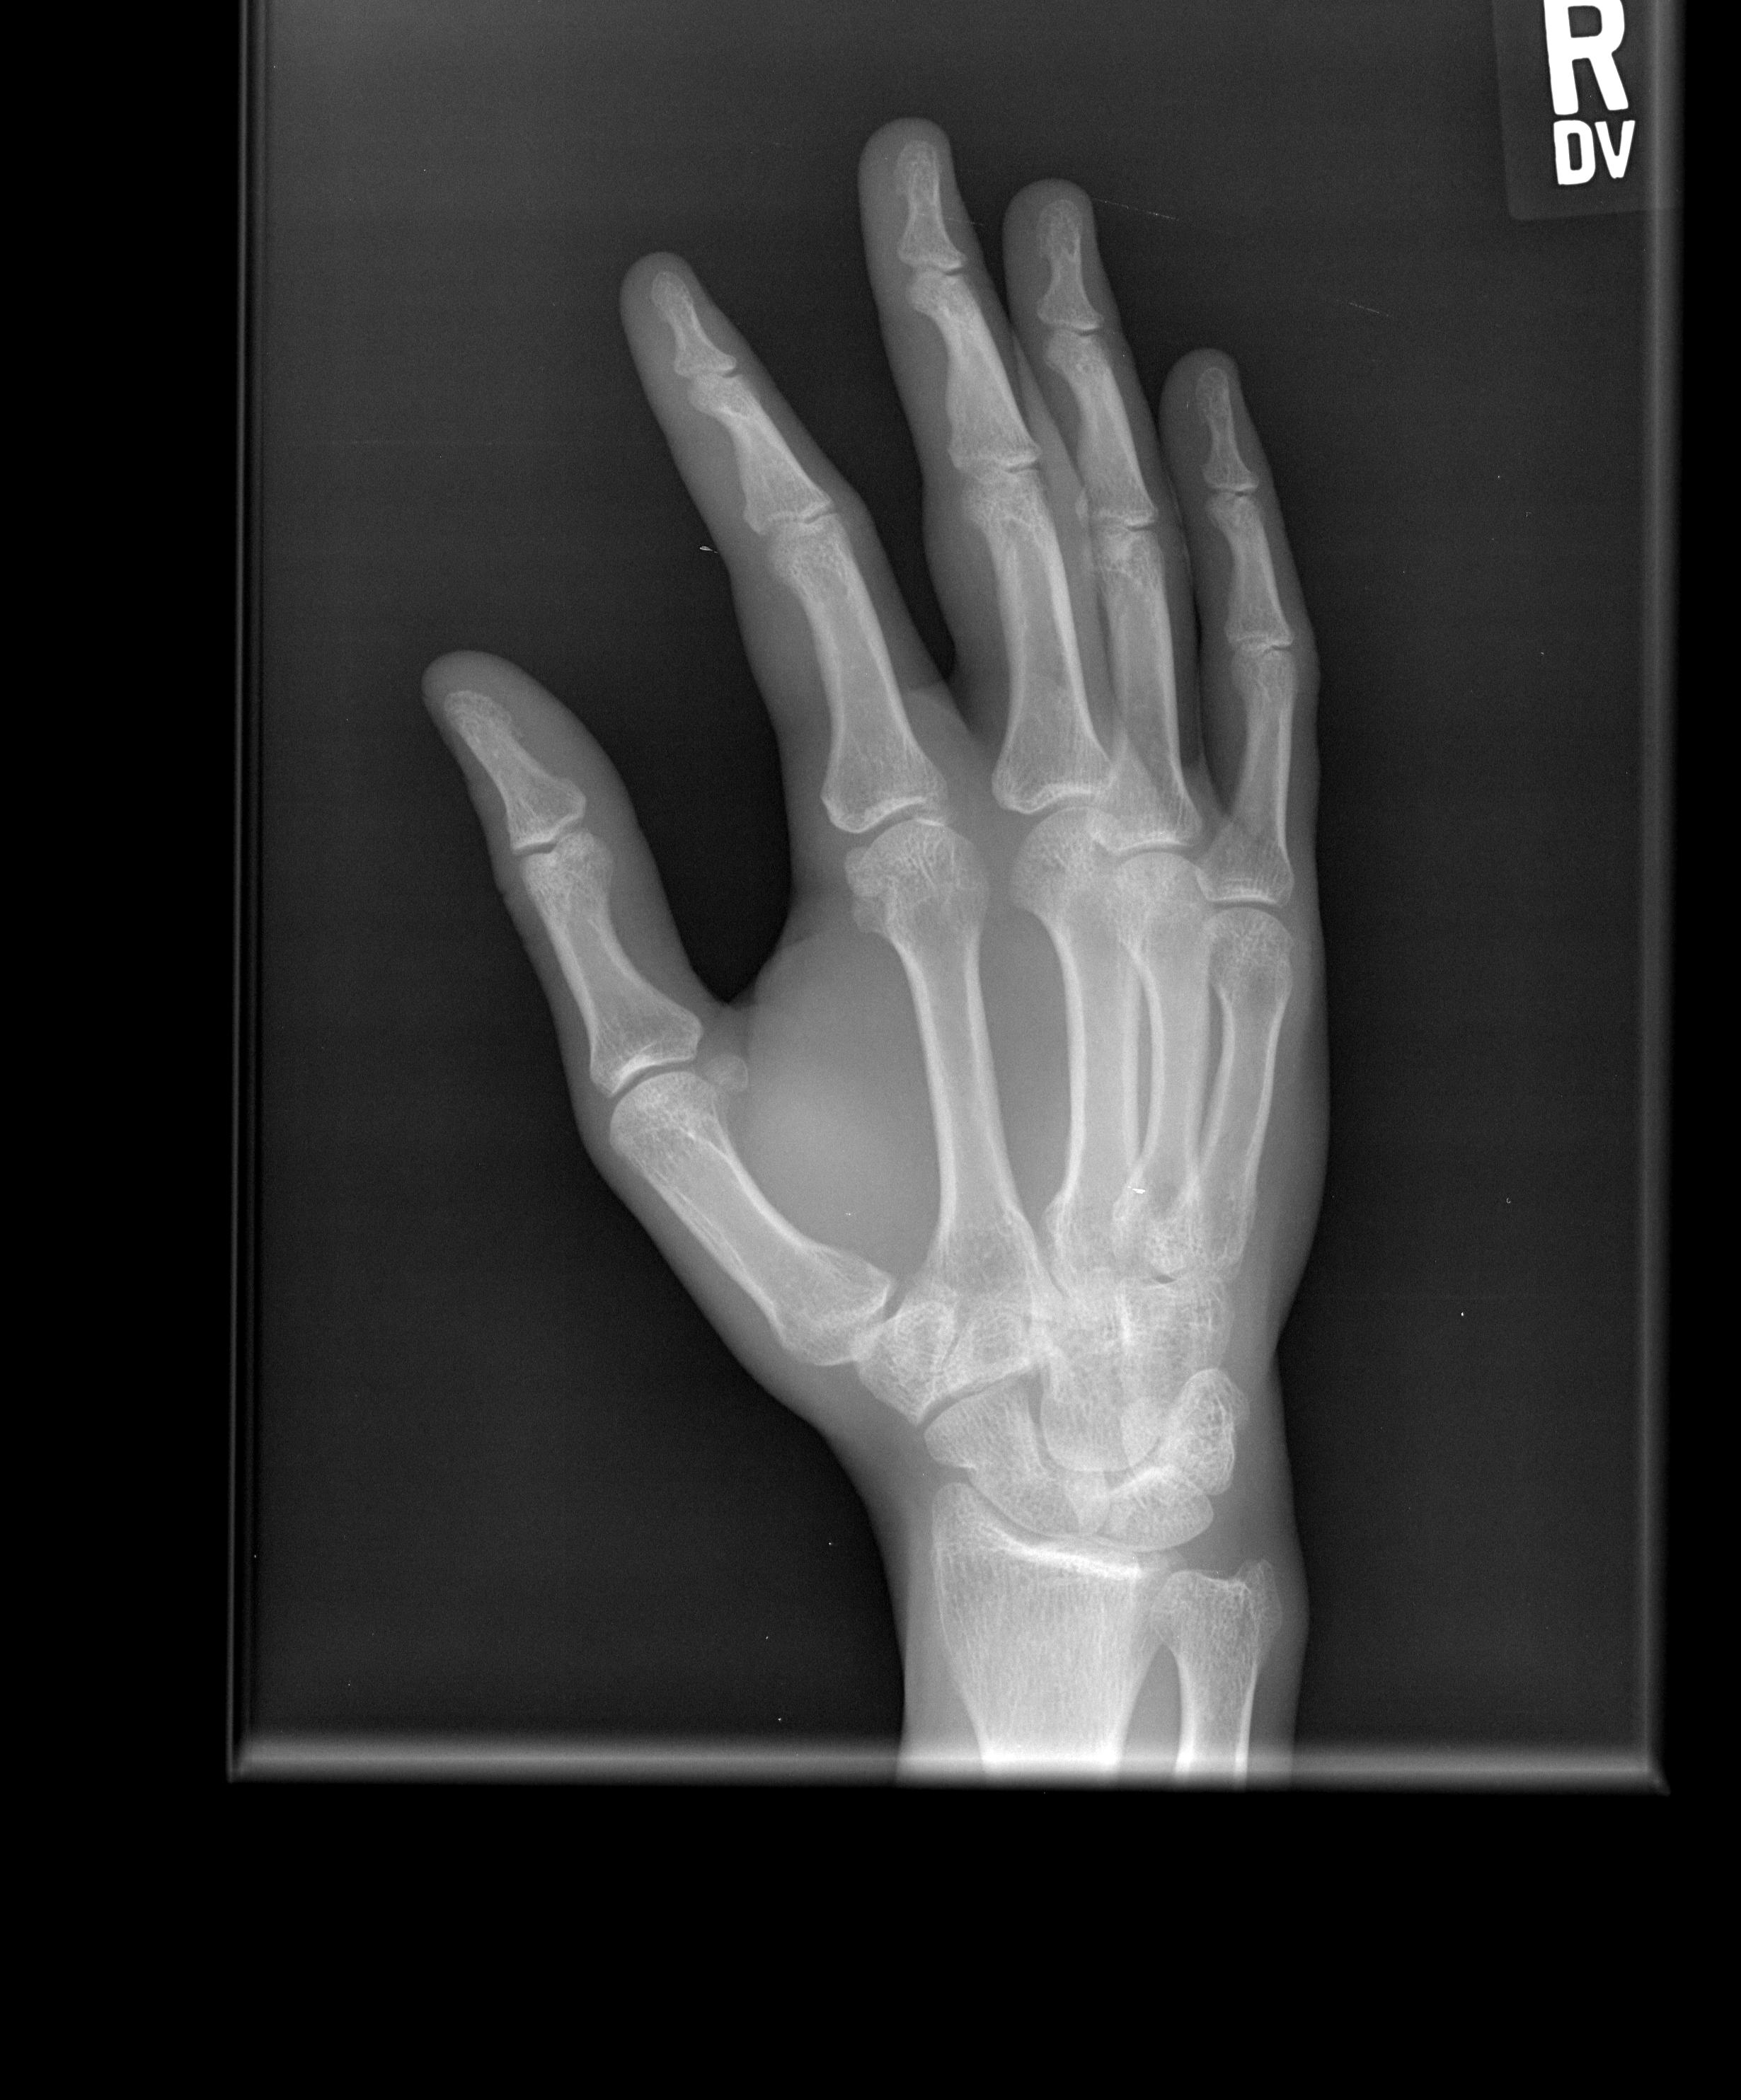

Human Adult Right Hand Bones Xray Image. Medical and Anatomy Hand Anatomy X-Ray Hand (anatomy) the hand is part of the upper limb below the forearm and wrist. On “anatomical parts” you can choose between two types of labels:. Benoudina s, normal radiographic anatomy of the hand. Fractures and dislocations are usually straightforward to identify, so long as the potentially injured bone is fully visible in 2 planes. The hand series consists of. Hand Anatomy X-Ray.

Hand Anatomy X-Ray . Although additional radiographs can be taken. Hand (anatomy) the hand is part of the upper limb below the forearm and wrist. On “anatomical parts” you can choose between two types of labels:. Frontal radiograph of the hand with labels. Benoudina s, normal radiographic anatomy of the hand. The hand series consists of posteroanterior, oblique, and lateral projections. Fractures and dislocations are usually straightforward to identify, so long as the potentially injured bone is fully visible in 2 planes. The hand comprises the metacarpal and phalangeal bones. In the supinated anatomical position , the palm is. Oblique radiograph of the hand with.

Hand Radiographic Anatomy wikiRadiography Hand Anatomy X-Ray Benoudina s, normal radiographic anatomy of the hand. Oblique radiograph of the hand with. Fractures and dislocations are usually straightforward to identify, so long as the potentially injured bone is fully visible in 2 planes. In the supinated anatomical position , the palm is. Hand (anatomy) the hand is part of the upper limb below the forearm and wrist. On. Hand Anatomy X-Ray.